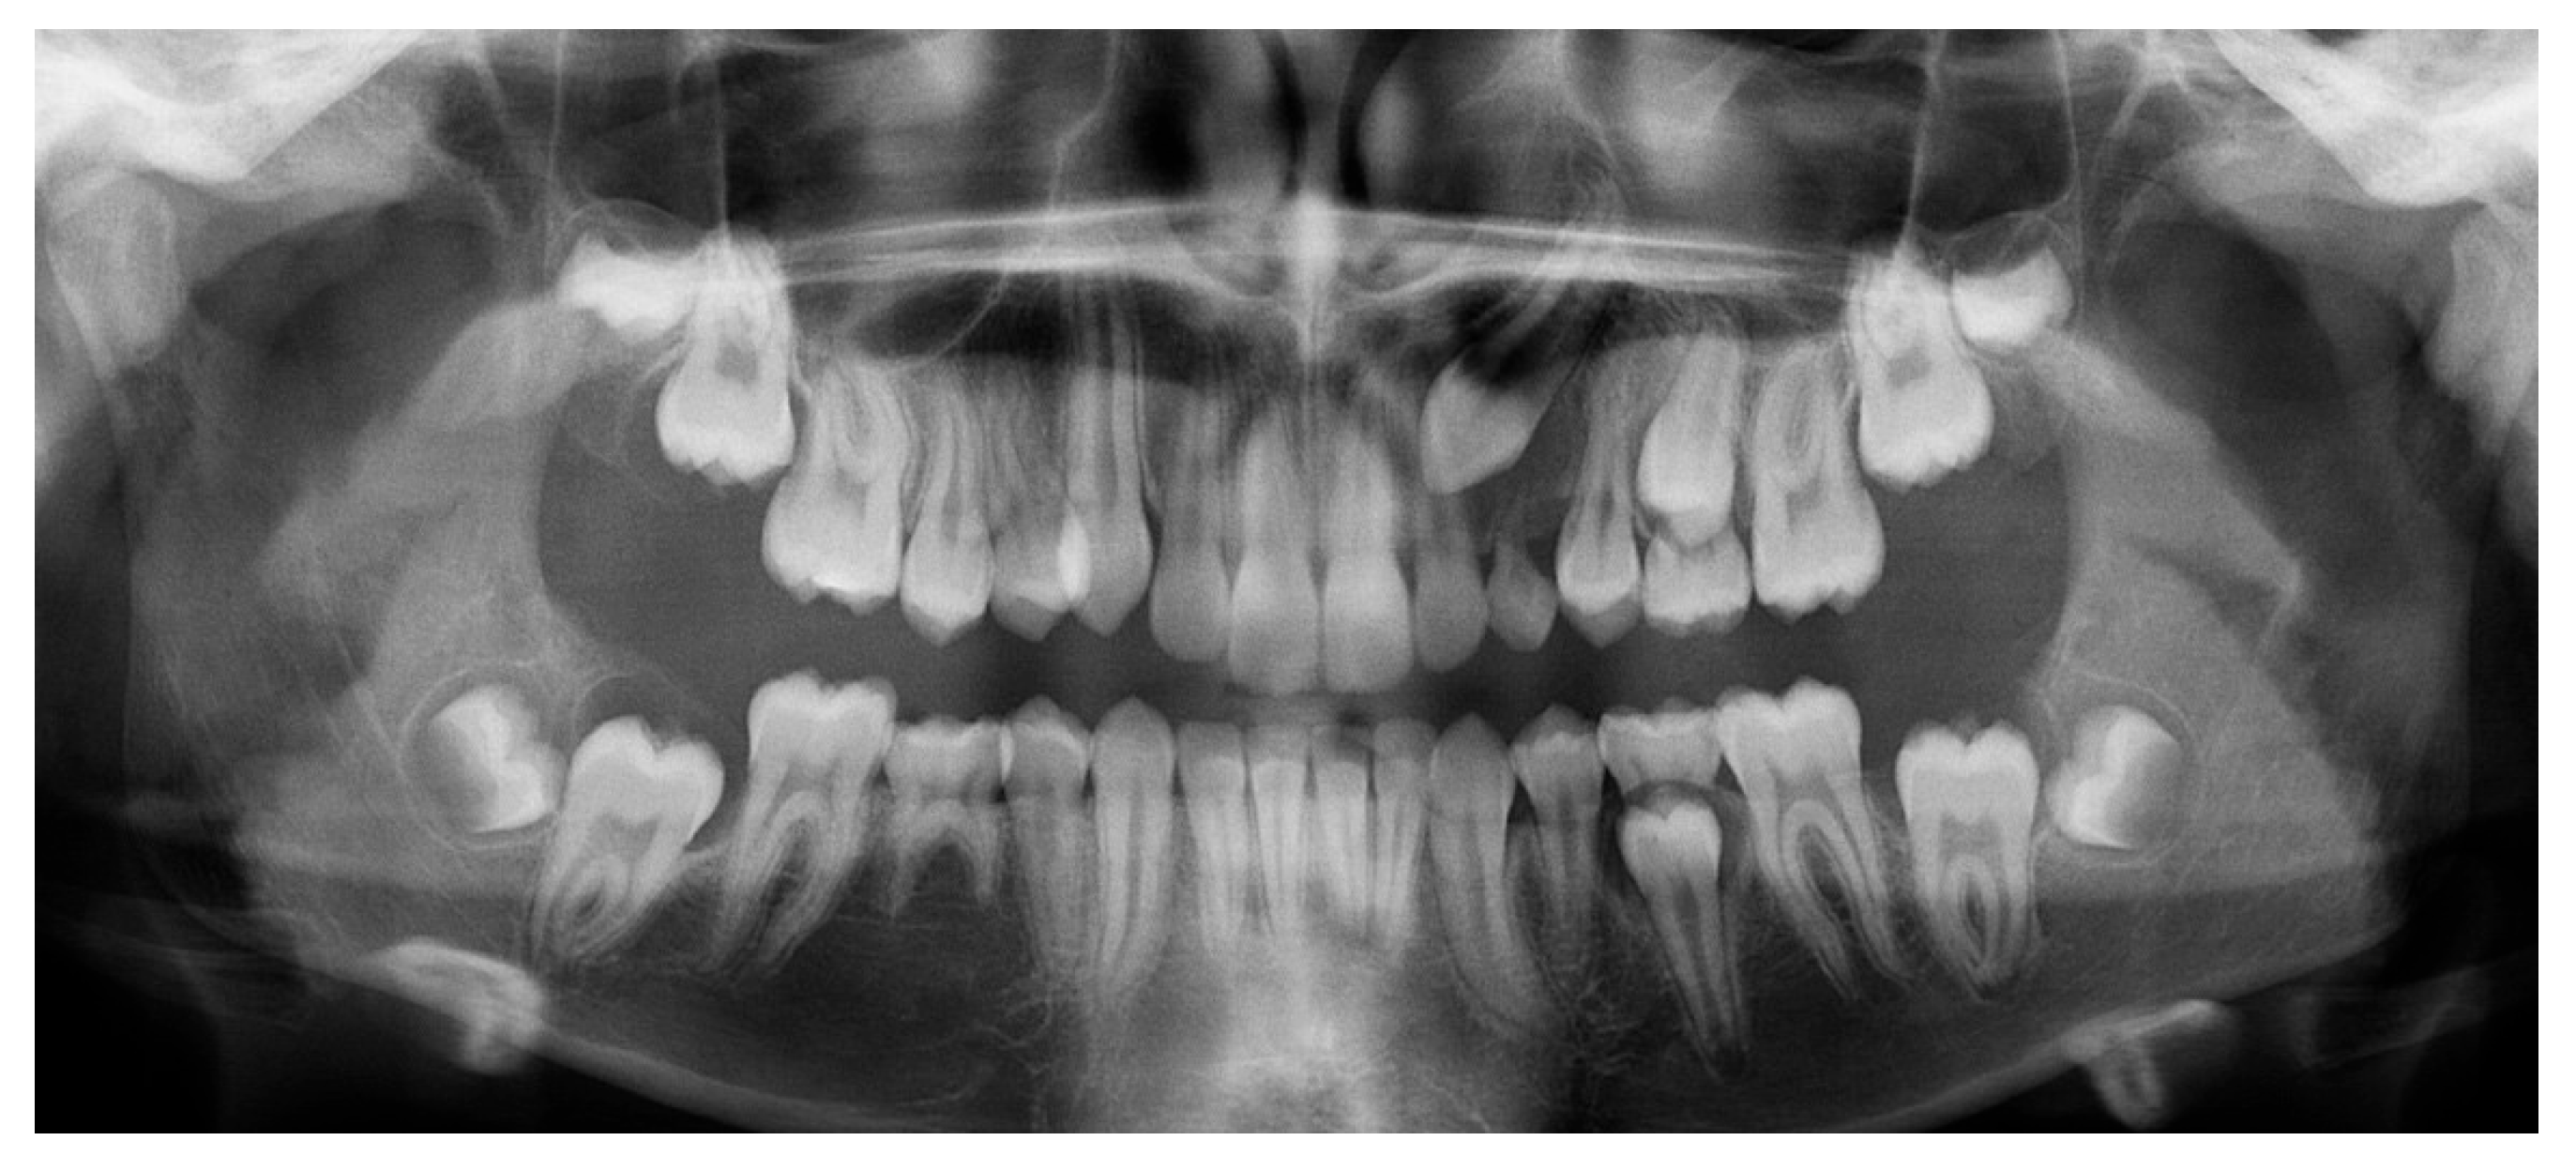

Since the IC is not visible in the initial STL, it was necessary to know its three-dimensional location. As performed in the other method, the initial CBCT scan (Figure 2) was opened in the program, and all teeth were segmented. Although Figure 2 shows the skull model, only the teeth segmentation is necessary for this method. A small cut was made to allow visualization of the IC (Figure 3).

Figure 2.

Initial CBCT scan.